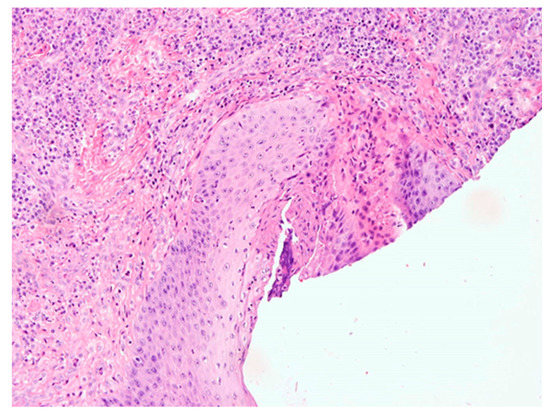

Pilot Study of Use of Nitric Oxide in Monitoring Multiple Dental Foci in Oral Cavity—A Case Report

by Magdalena Wyszyńska, Przemysław Rosak, Aleksandra Czelakowska, Ewa Białożyt-Bujak, Jacek Kasperski, Maciej Łopaciński, Nour Al Khatib and Małgorzata Skucha-Nowak

Healthcare 2022, 10(2), 195; https://doi.org/10.3390/healthcare10020195 - 20 Jan 2022

Background: The most common cause of implant loss and deteriorating restoration aesthetics is infection and chronic inflammation of the tissues around the implants. Inflammation in the oral cavity, confirmed by clinical and histopathological examination and determination of exhaled nitric oxide, is a situation [...] Read more.

Background: The most common cause of implant loss and deteriorating restoration aesthetics is infection and chronic inflammation of the tissues around the implants. Inflammation in the oral cavity, confirmed by clinical and histopathological examination and determination of exhaled nitric oxide, is a situation which may cause the complications on the whole human body. Elimination of the patology in the oral cavity in some cases is the only resonable treatment. The aims and objectives of our work is to present a gradual treatment of advanced infalmmation and present huge reduction stamp of inflammation measured with marker nitric oxide (NO) in exhaled air. Materials and Methods: Simple treatment containing elimantion of pathology in the oral cavity was conducted. Patient that came to the dental practice suffered from the inflammation caused by lack of proper hygiene. First aid in this situation was to eliminate the inflammation which may affect negatively for general health. At first visit full hygienization was performed, at the second visit roots of abutment teeth and implants were removed under local anesthesia along with cystic changes. Results: The hygiene precedures and extraction of the unsteady inflammationprosthetic restorations significantly decreased the level of NO in exhaled air. Conclusions: During the examination of the patient coming to the dental practice great attention should be paid to the coexistence of pathologies related to the oral cavity. Omission of a dental examination and possible elimination of odontogenic foci may affect the implication of the results of general diagnostics and subsequent treatment. Measuring the level of NO on exhaled air seems to be useful diagnostic method. Full article